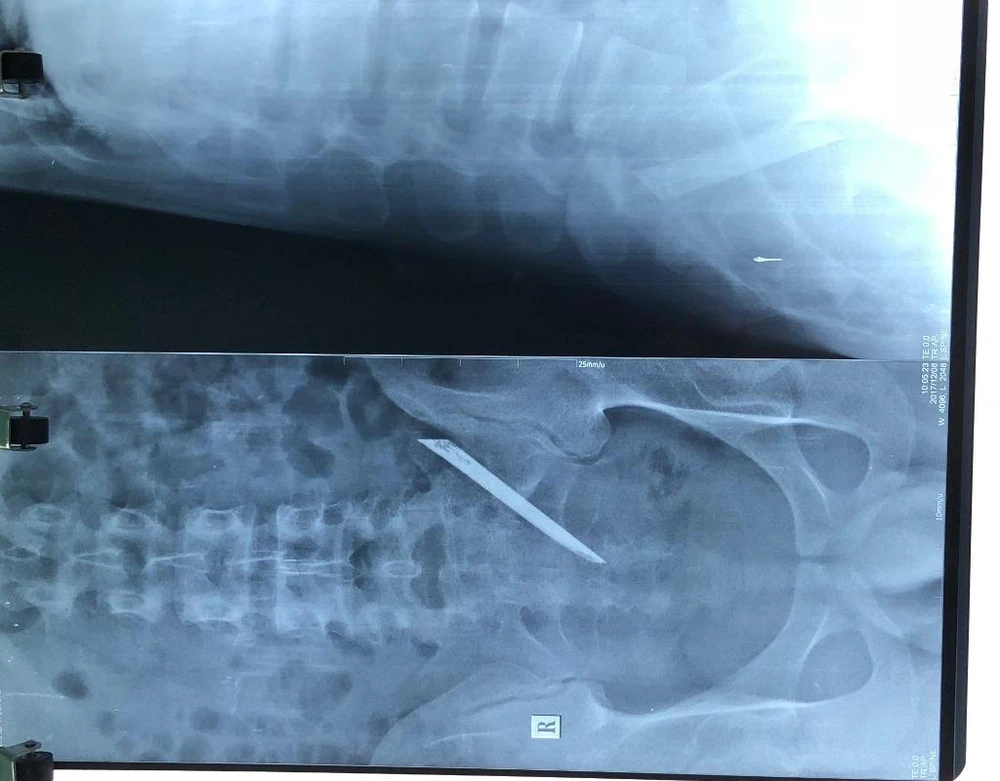

Kết quả sau khi chụp phim và làm các xét nghiệm, bác sĩ chẩn đoán anh L. có dị vật vùng lưng, đoạn từ L5-S1 xuống đến vùng cùng cụt, phải phẫu thuật.

Phim chụp cho thấy có dị vật trong cơ thể bệnh nhân

Phim chụp cho thấy có dị vật trong cơ thể bệnh nhân. Ảnh: BV cung cấp